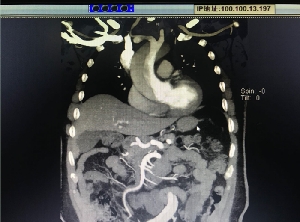

歷經(jīng)10小時(shí),心臟大血管外科“超級手術(shù)”成功救治Stanford A型主···